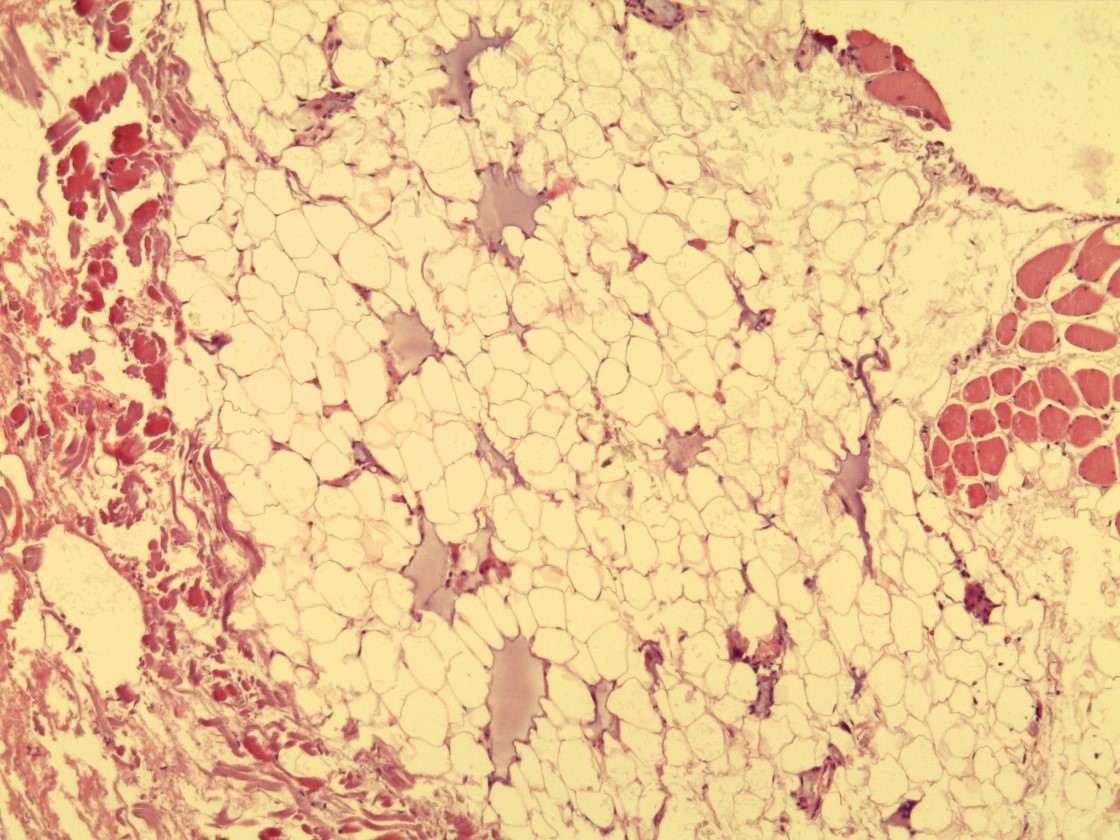

Гистологическая картина ПАМС до начала комплексного лечения была типичной и совпадала с описаниями других исследователей [22–26]. По всем полям визуализировали скопления гомогенных инородных тел (ПААГ), характер которых зависел от количества введенного геля, глубины и давности его залегания в мягких тканях, а также интенсивности его межтканевой миграции (рис. 1). Вокруг больших массивов безоболочечного имплантата, в основном сохранившего свою гомогенную базофильную структуру, прослеживалась тонкая соединительнотканная капсула толщина 50–120 мкм. Она состояла из нескольких слоев коллагеновых волокон и фибробластов (рис. 2). Толщина капсулы была неодинаковой на всем протяжении. На некоторых участках заметно выраженное ее истончение, разволокнение, дегенеративные изменения вплоть до полного перерыва (рис. 3). Последнее было особенно заметно у пациенток с длительным, свыше 10 лет, анамнезом «гелевой» болезни, а также при миграции ПААГ в соседние области.

Рис. 3. Биоптат ткани молочной железы: определяется зона дезорганизации капсулы вокруг гелевых масс. Окраска гематоксилином и эозином (×200).